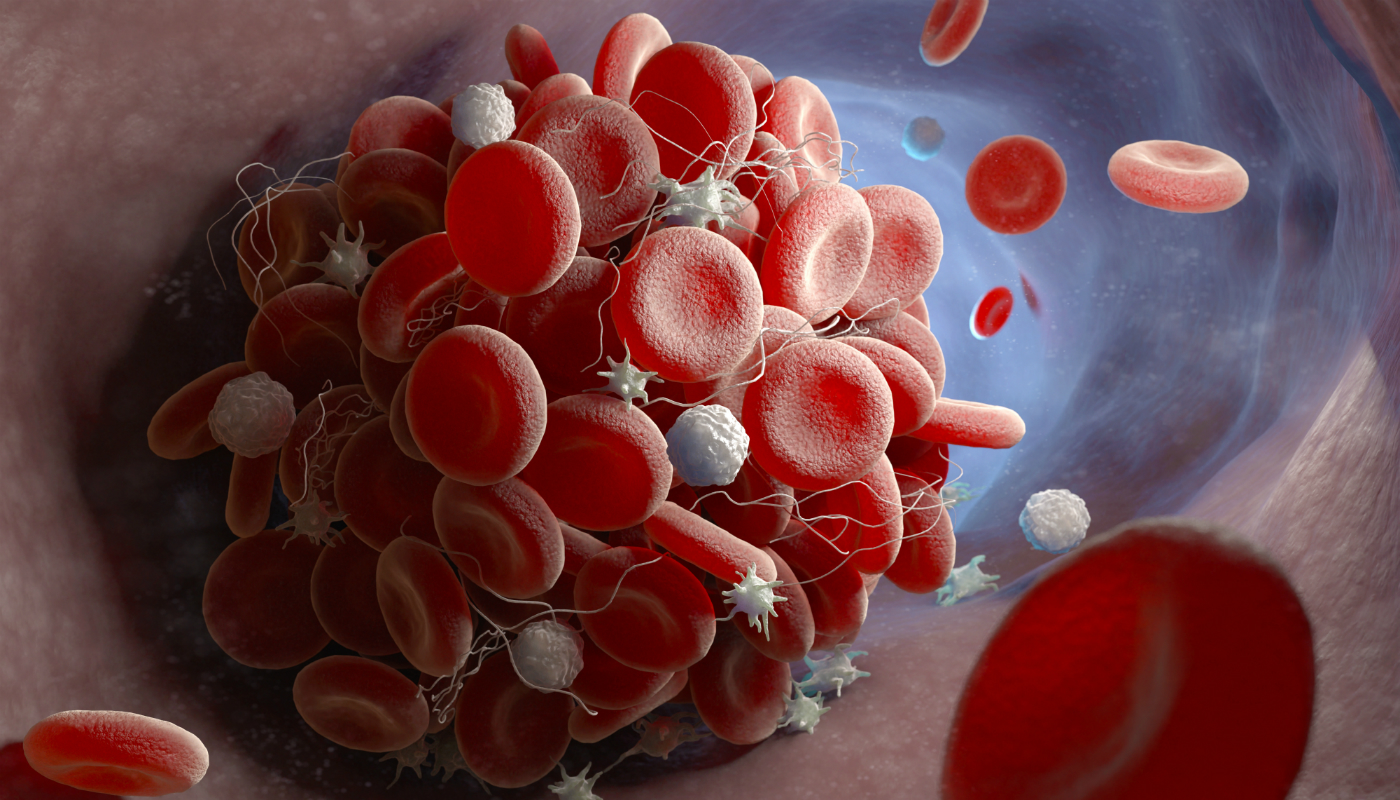

Apesar de compartilharem um nome, a embolia gasosa e a tromboembolia não são a mesma coisa. Isso porque, na gasosa, há obstrução de vasos sanguíneos por bolhas de ar e, na tromboembolia, esta obstrução de vasos ocorre por conta de coágulos. Enquanto no segundo caso é possível muitas vezes utilizar medicamentos para dissolver os coágulos, não há remédios que possam retirar o gás da corrente sanguínea.